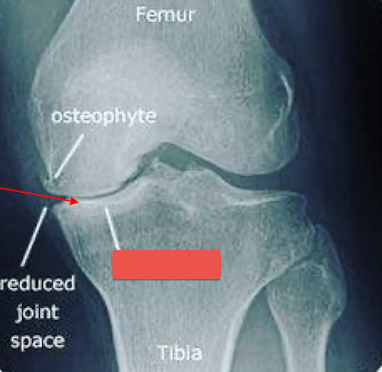

Label the image

intra-capsular soft tissue swelling

osteophytes

enthesophytes

subchondral erosions

intra-articular calcified bodies

subchondral sclerosis

subchondral cysts

joint space narrowing

What condition? What main feature does the image show?

Stifle DJD (likely from a cruciate ligament rupture)

intracapsular swelling (cranial displacement of infra patellar fat pad and caudal displacement of fascial stripe)